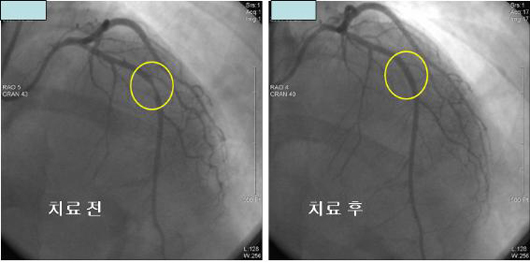

#. ɱ̶ٰ ?

- ⱸ 뵿ƿ ̶ ϸ (ɱ) ȴ. ¸ Ȱ ϱ Ͽ ȯŰ ü ̳ ҳ Ҹ ƾ ϹǷ װ ſ ߿ϴ. ο ǰ ϰ Ǹ ɱ ¿ ̸ Ǵµ ̷ ȯ ̶ Ѵ.

ƿ ưȭ ǰ ̿ Ͽ ü, ưȭ öũ Ŀ̳ ־ Ϻΰ , ɱټ ܵǾ ( ) Ű ɱ̶ٰ մϴ. ۺ а, 帶 縦 ʷ ɼ ϴ. ȯ ȯ 50-70% ź ϰ ִ ȭǾ ̰, 15-20% ϴ ִµ ̴ ַ 索 ȯڳ , ε Ÿ ִ.

#. ɱٰ ? - 漺 Ǵ ȭ̴, ߸ ̷ ħ ϰ ǰ ӵǸ ڲ Ǯ ó ϴ ħ ܴ Į ȴ. ̷ ǰ ɱٿ Ǵ Ͽ, 䱸 Ȳ Ұ ɱ Ÿ ȴ.

ɱ , ִ ưȭ ջ ް ǰ ӿ ִ ǰ ̿ پ Ƕ̶ Ҹ ϰ Ǹ ɱ װ Ǿ ɱ 翡 ̸ ȴ.

ɱٰ Ǵ ưȭ ݵǴµ, ӵ ־ , , , 索 ȴ. , , ݷ ưȭ 3 ڶ ϸ ̷ 3 ̿ܿ ռ 索, , , Ʈ ưȭ Ų.

ۿ ü ̳, ƿ, 뵿 Ǹ ȯ ȯ ִ.

#. ɱٰ

- ũ Ҿ 2 ִ. 쿡 հ Ѱ Ȥ ȣϴ 찡 ȯڴ ̰ йϴ 谨, ̴ , ſ, , ¥ , Į Ȥ , ǥѴ. Ȥ , , , , , ް ĵǸ, δ ȣ, Ƿΰ, , ǽ ȣϴ 쵵 ִ. ̷ Ȱ üȰ, , Ļ , ۽ ( ҿ ߿ ̵ ), 踦 ǿ ƹڼ ϰų л 쿡 Ÿ ȴ. ̶ Ÿ Ͻ(2-15)̾ ϸ 3-5 , Ʈα۸ ϸ 밳 1 ̳ ɴ´. 20 30 ̻ ӵǴ , ӽð 5 ̳̰ų, ȣ , ϴ , ҵǴ , ̳ ҵǴ , 2cm , ؾ ̴. Ҿ ı ϳ ɱٰ ̿ ġѴ. ɱٰ ȯ 30-60% Կ Ҿ Ѵ. ÿ ϰ, ӵǰų Ƚ Ʈα۸ ϴ 츦 Ѵ.

ٸ ִµ ̴ Ȥ ̸ ħ ȣϰ ǰ Ʈα۸ Į .

ɱٰ ϳ 30 ̻ ξ Ÿµ, ̸鼭 ϰ Ÿ Ǵ ٰ ϸ ġ ϴ Ȳ ǥȴ. Ȱ üȰ, , Ļ , ۽ ( ҿ ߿ ̵ ), 踦 ǿ ƹڼ ϰų л 쿡 Ÿ Ǹ ӽð 30 ̻ ӵȴ. ̶ Ʈα۸ ؿ ־Ƶ ʴ´. ̳ , ̱ Ͽ ǰ ʿϴ. Ư 索 ΰ ִ ȯڿ ߺϱ ϹǷ ʾ 찡 .

ɱٰ ȯ 밳 ܰ ġḦ Ѵ. ϴ ݺǸ Ǹ ã ϰ ˻縦 ƾ Ѵ. ⺻ ˻δ ݷ ˻, ɱȿ ˻ ִ. Ư ̵ ˻縦 ı ϴ ſ ߿ϴ. Ҿ ɱȿ ġ ST δٸ ST ɱٰ ﰢ ʿϴ. ɱȿ ġ ST ST ɱٰ̳ Ҿ ﰢ Կ ġᰡ ݵ ʿϴ.

ǽɵ ˻, 24ð Holter ˻, (Ȥ ) ˻, ˻ ̿Ͽ ϰ ȴ. ֱٿ CT˻縦 3 ̰ ִ.

- CT -

Ȯ ˻ Ÿ Ȥ ȸ ̿Ͽ úα ġŰ Ͽ , Ȯϴ ̴.

- -

#. ɱٰ ġ - ȯ ġῡ , Ϲݿ, , ü ִ. ưȭ ų ִ ġῡ ݵ ݵǾ Ѵ. Բ ǥ ü ϵ ϰ, ڴ ݵ 踦 Ѵ. ΰ Ͽ 帶 30-40 ˷ ִ. . 索. ̵ ȯ ġ ȯ ġ 濡 ſ ߿ϴ. ݷ δ ¡, Ұ, , , 븥, , ǥ̸ ̵ 븦 ϰ Ĺ⸧ , , ⸧ ȭ 븦 ø ٶϴ.

Ϲ . ù°, ü Ȱ ϸ ־ ȯڰ Ҿ ϹǷ Ͽ ϵ Ѵ. ħ. ȭ Ƿ ħ̳ Ļ Ŀ ӵ ٵ, 2ð ̻ ¿ Ѵ.

δ 꿰, Ÿ-Ƶ巹 ü , Į, ƽǸ ִ. ﰢ ʿ ɱٰ ִ. ð ߿ѵ 2ð 3ð ̳ ȿ ݵ ݱ ִ Ȯϰ ϴ ߿ϴ.

üġ Ÿ Ȥ ո Ͽ dz dz Ȯ κ а ϴ Ȯ (Ʈ) ־ ְ ϴ Ʈ Լ Ѵ. ̴ Ͽ ϴ ġῡ 밡 ʿ 밳 üð 1~2ð ̸̳ Ư ݼӸ ߵ ġ ſ ֱ θ Ǵ ġ̴.

üġ ذ ȯ Ͽ ų ̽ϴ ƿȸ ؾ Ѵ.

ȯ ġĢ 캸 켱 ġḦ ϰ Ȯ˻ ߰ߵ ݼӸ Լ Ѵ. ı ϰ Ȯ ؾ ϸ Ư ɱٰ ִ Ȥ Ȯ ݼӸ Լ Ѿ Ѵ.